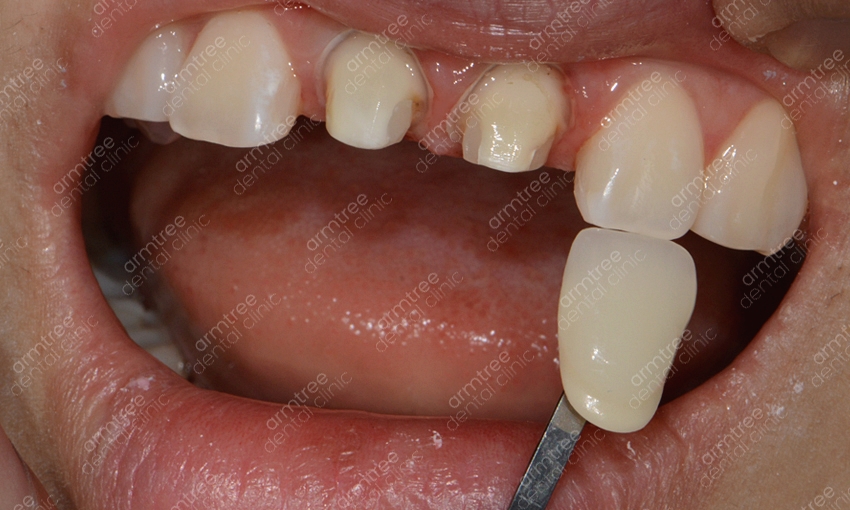

앞니변색으로 미백을 고려하시지만 모든 경우에 해당하여 진행할 수 있는 시술은 아니에요. 치아가가 활력을 잃어 변색이 된 경우에는 실활치 미백으로 치료하는 것이 보통의 경우이지만 정도가 심각한 경우에는 미백 시술만으로 호전되지 않기 때문에 라미네이트나 올세라믹 같은 심미보철치료가 필요할 수 있었어요. 치아 신경 손상이 진행되었지만 신경치료를 제 시기에 하지 못하고 방치한 경우 중 일부의 치아에서는 신경조직이 말라 없어져 버리는 경우가 생기는데 이러한 경우를 근관 폐쇄라고 하는데요. 신경치료의 원리가 치아의 머리부분에서 신경조직에 이르는 구멍을 만들어 감염된 신경조직을 제거하는 방식으로 진행하기에 이렇게 신경이 말라서 없어진 경우에는 신경 치료 자체가 불가능하게 되고 그러한 이유로 실활치미백도 진행할 수 없게 되는데요. 그럴 땐 치아 표면에 인조 손톱 같은 도재를 붙여주거나 치아 전체를 크라운으로 씌어 주는 시술을 진행하게 되는데 이러한 심미보철치료는 치아의 색상을 원하는 대로 연출할 수 있을 분 아니라 주변 치아의 배열까지 가지런하게 만들어 줄 수 있어 치아 교정과 비슷한 효과를 기대해 볼 수 있다는 장점을 가지고는 있었어요. 하지만 기능적인 면에서는 자연치처럼 중요한 것이 없기에 어떠한 심미적인 치료가 더 효과적인고 본인의 케이스에 적합한지 상담을 받아보시고 결정하는 것이 필요한 일이었었어요.

실활치미백은 치아가 전체적으로 변색되어 하는 일반적인 치아미백과는 다른 것이 특정치아 특히 앞니만 변색되거나 1-2개의 치아의 색이 변한 경우 진행하는 경우가 많은데요. 치아 1-2개의 색만 검게 변한다면 전체적으로 누렇거나 하얗지 못하게 되었을 때 보다 더 어색하거나 튀어서 도드라지게 보일 수 있기에 적절한 치료를 통해 주변 치아의 색과 유사하도록 해주는 것이 효과적이에요. 또 일반적인 치아미백이라면 미백제의 농도 조절이나 미백 광선의 조사방법이 중요한데 실활치미백은 먼저 신경치료가 선행되어야 하기에 보다 정교한 시술이 필요해요. 신경조직은 여러 갈래로 나뉘어져 섬세한 치료를 요하는 시술이기 때문인데요. 신논현역치과 아름드리치과에서는 3D 첨단 장비를 구비하고 있어 세세한 부분까지 신경치료를 진행할 수 있을 뿐 아니라 항시 임상경험이 풍부한 의료진이 대기하고 있어 정확하고 안전한 시술을 기대할 수 있었어요. 또 신논현역치과에서는 환자 개인마다 다른 환자의 구강환경에 맞춰 1:1 맞춤 플랜을 세워 치료를 진행하고 있었어요. 아름드리치과는 앞니 단일 치아의 변색일 때에는 외상으로 인한 치아 신경의 염증, 치아의 신경인 치수 잔사 등 미세한 염증이 존재하는 경우, 기존 신경치료 후 레진 수복 후 레진 수복재료사이의 미세누출로 염증이 생긴 경우 등 다양한 경우의 원인이 있을 수 있어요. 그렇기에 보다 정확한 진단 검사와 그에 따른 치료계획을 수립하는 것이 중요한 과정이라 볼 수 있었어요. 미백치료의 경우 집에서 셀프로도 많이들 진행하시지만 미백 후에 효과가 별로 없다거나 1-2의 치아만 유독 변색이 심하다면 집에서 직접 하는 방식으로는 치료가 불가능하기에 꼭 신논현역치과 아름드리치과를 내원하시길 권해드리겠어요.